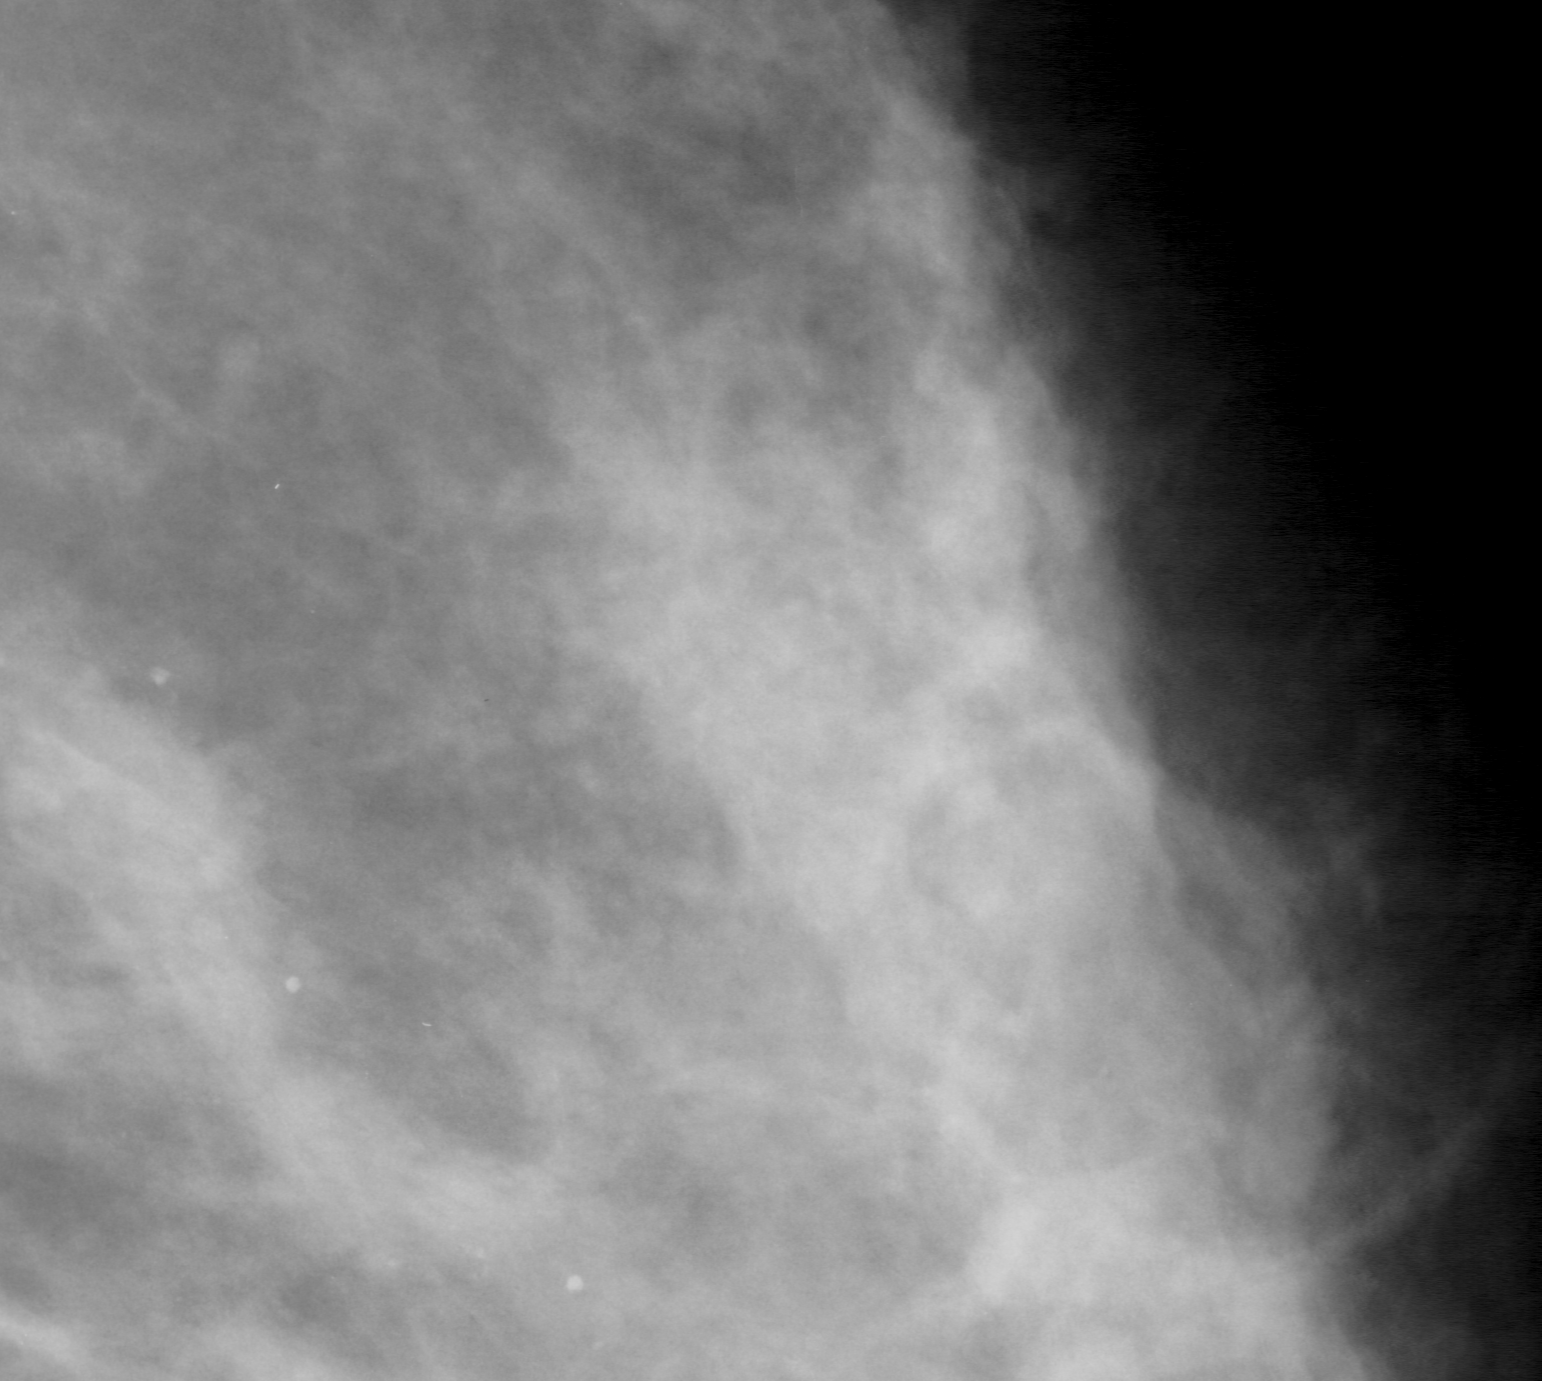

In our experiments, we use the Digital Database for Screening Mammography (DDSM) [4], a collaboratively maintained public dataset at the University of South Florida. It comprises approximately 2500 studies each containing both mediolateral oblique (MLO) and craniocaudal (CC) views of each breast. Each image is grayscale and accompanied by a mask specifying the region of the pre-segmented mass if present. Examples of benign and malignant masses are shown in Fig. 1.

Deep learning models often lack interpretability and as such are hard to adopt for practical use in medical settings. [21] describe a methodology to visualize saliency maps which show the regions of an image the network is sensitive to when making predictions. This is performed by computing the gradient of the image with respect to the unnormalized class scores. Regions with larger gradient indicate higher contribution to the prediction (brighter in Fig. 3). Both the AlexNet and GoogLeNet learn to attend to the edges of the mass, which is a high-signal criterion for diagnosis, while also paying attention to context.